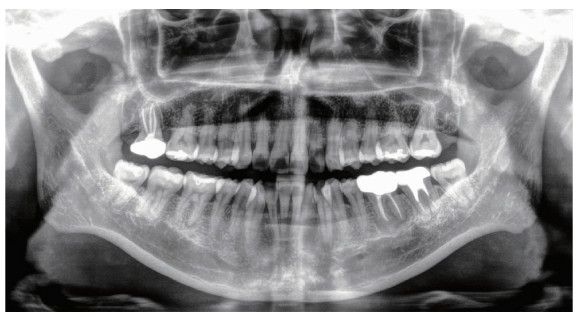

Figure 4

Panoramic radiograph at 1-year follow-up"